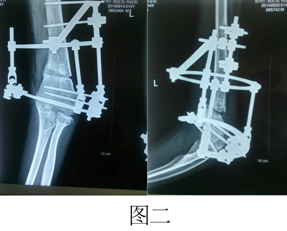

病例二:刘XX,男,14岁, 左肱骨髁上骨折,骨骺损伤,肘内翻畸形。

术前(图一)

矫形过程中(图二)

矫形四个月体表(图三)